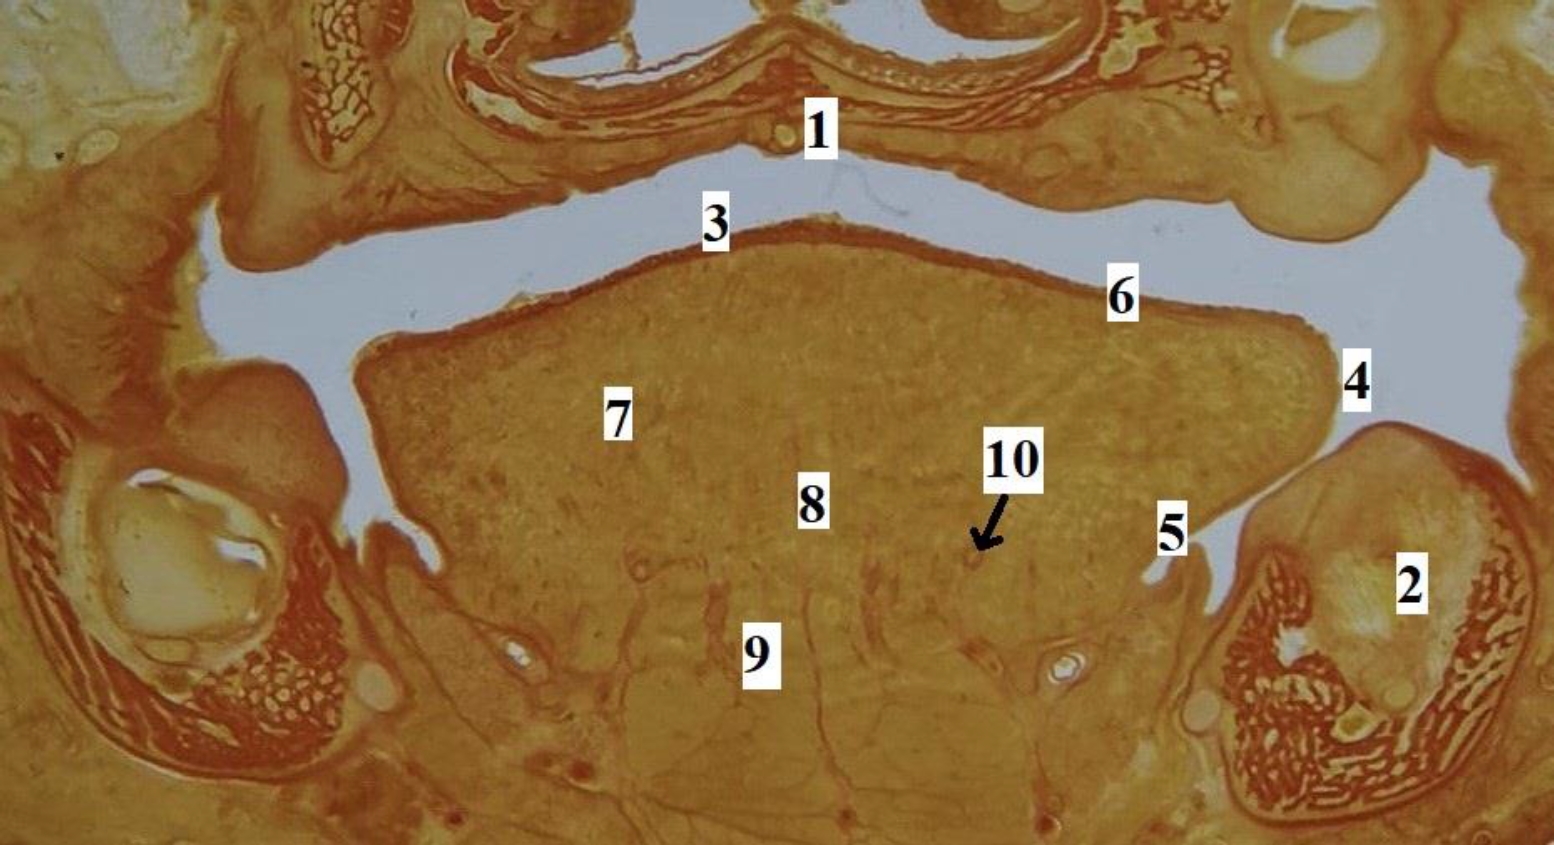

Язык человека в промежуточном плодном онтогенезе сформирован, макроскопически определяются все структурные элементы органа (рис. 2). На гистотопограммах визуализируется макромикроскопическая структура и микротопографические взаимоотношения мышц, сосудов, слизистой оболочки, стромального компонента языка (рис. 3). Линейные параметры языка, а также их описательная статистика представлены в табл. 2.

Рис. 3. Язык плода человека. Фронтальная гистотопограмма. Фото под микроскопом MicroOptix MX-1150, ок. ×10, об. 1. Возраст – 22 недели, пол мужской. Окраска по Ван – Гизону: 1 – твердое нёбо; 2 – нижняя челюсть; 3 – спинка языка; 4 – край языка; 5 – эпителий слизистой оболочки нижней поверхности языка; 6 – специализированный эпителий спинки языка; 7 – мышечные волокна поперечной мышцы языка; 8 – перегородка языка; 9 – мышечные волокна подбородочно-язычной мышцы; 10 – глубокая артерия языка